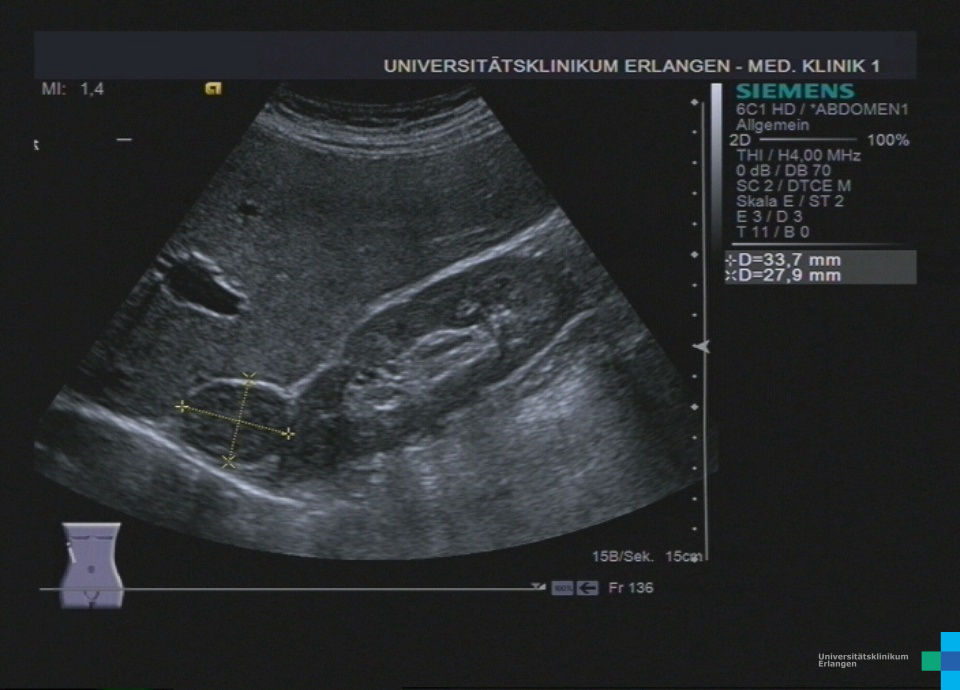

- Adrenal: CT/MRT Abdomen

CT/MRT: Adenom < 10 HU (fettreich), Karzinom > 20 HU, suspekt bei schnellem Wachstum